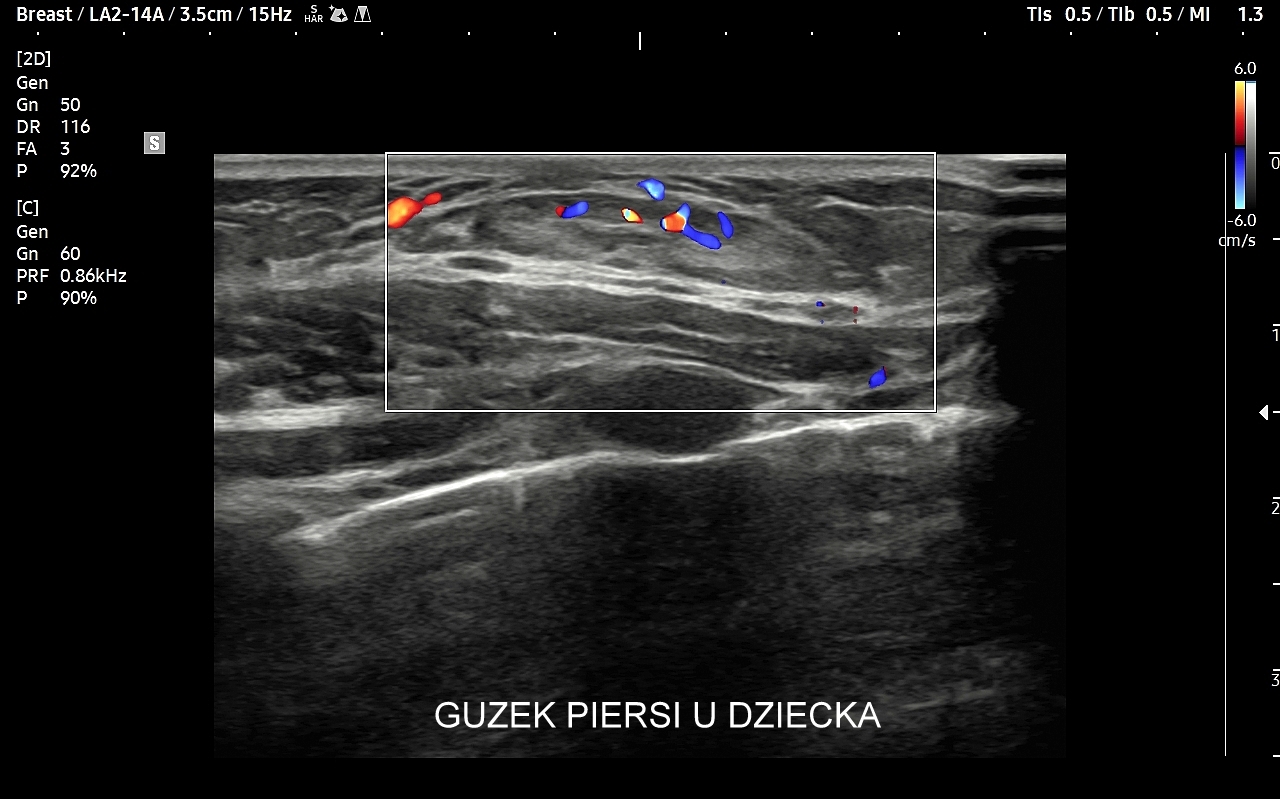

USG piersi u dzieci

Najczęstszym wskazaniem do badania gruczołu piersiowego u dziewczynek jest stwierdzenie przedwczesnego dojrzewania płciowego (ang. precoxious puberty), inaczej pokwitania,  w tym przedwczesnego rozwoju gruczołów piersiowych (łac. thelarche praecox), które jest najczęstszą formą przedwczesnego pokwitania. Badanie USG jest w takiej sytuacji częścią diagnostycznego postępowania endokrynologicznego. W rzadszych przypadkach powiększenia gruczołów piersiowych u dzieci znajdowane są guzy lite, np. tłuszczako-włókniaki.